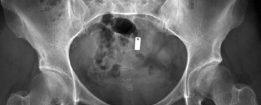

Revision THA Acetabulum Paprosky Type IIIA. ARMD with Metallosis with Severe Periacetabular Osteolysis and Co…